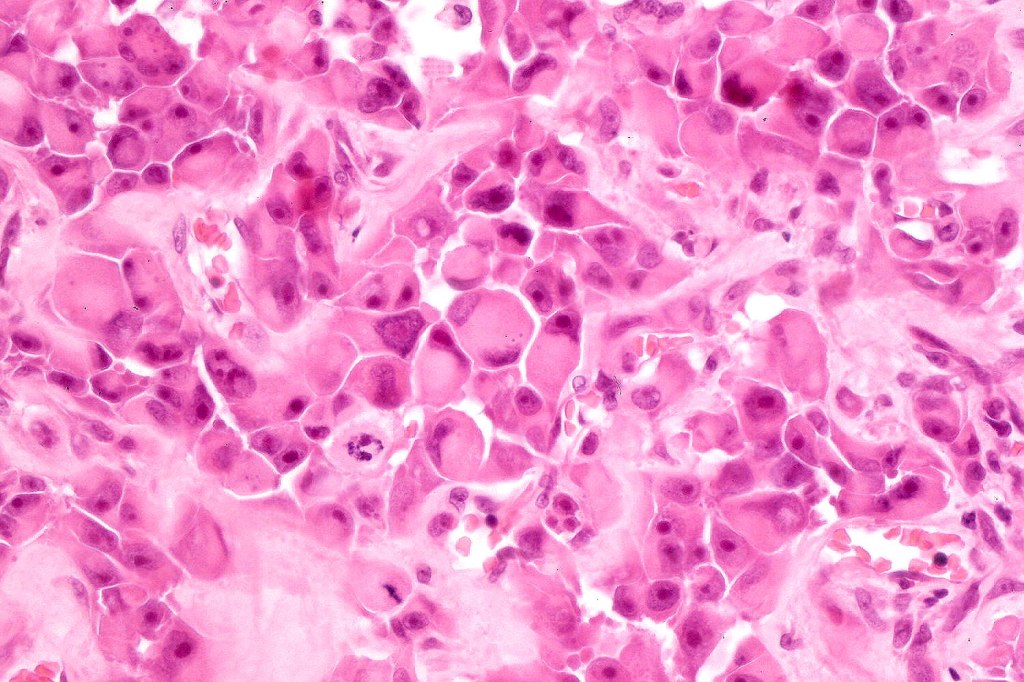

•Characterized by pleomorphic tumor cells with large eosinophilic, hyaline globular inclusions and eccentric vesicular nuclei containing prominent nucleoli, mitoses often conspicuous

•Very sparse melanin pigment may be identified